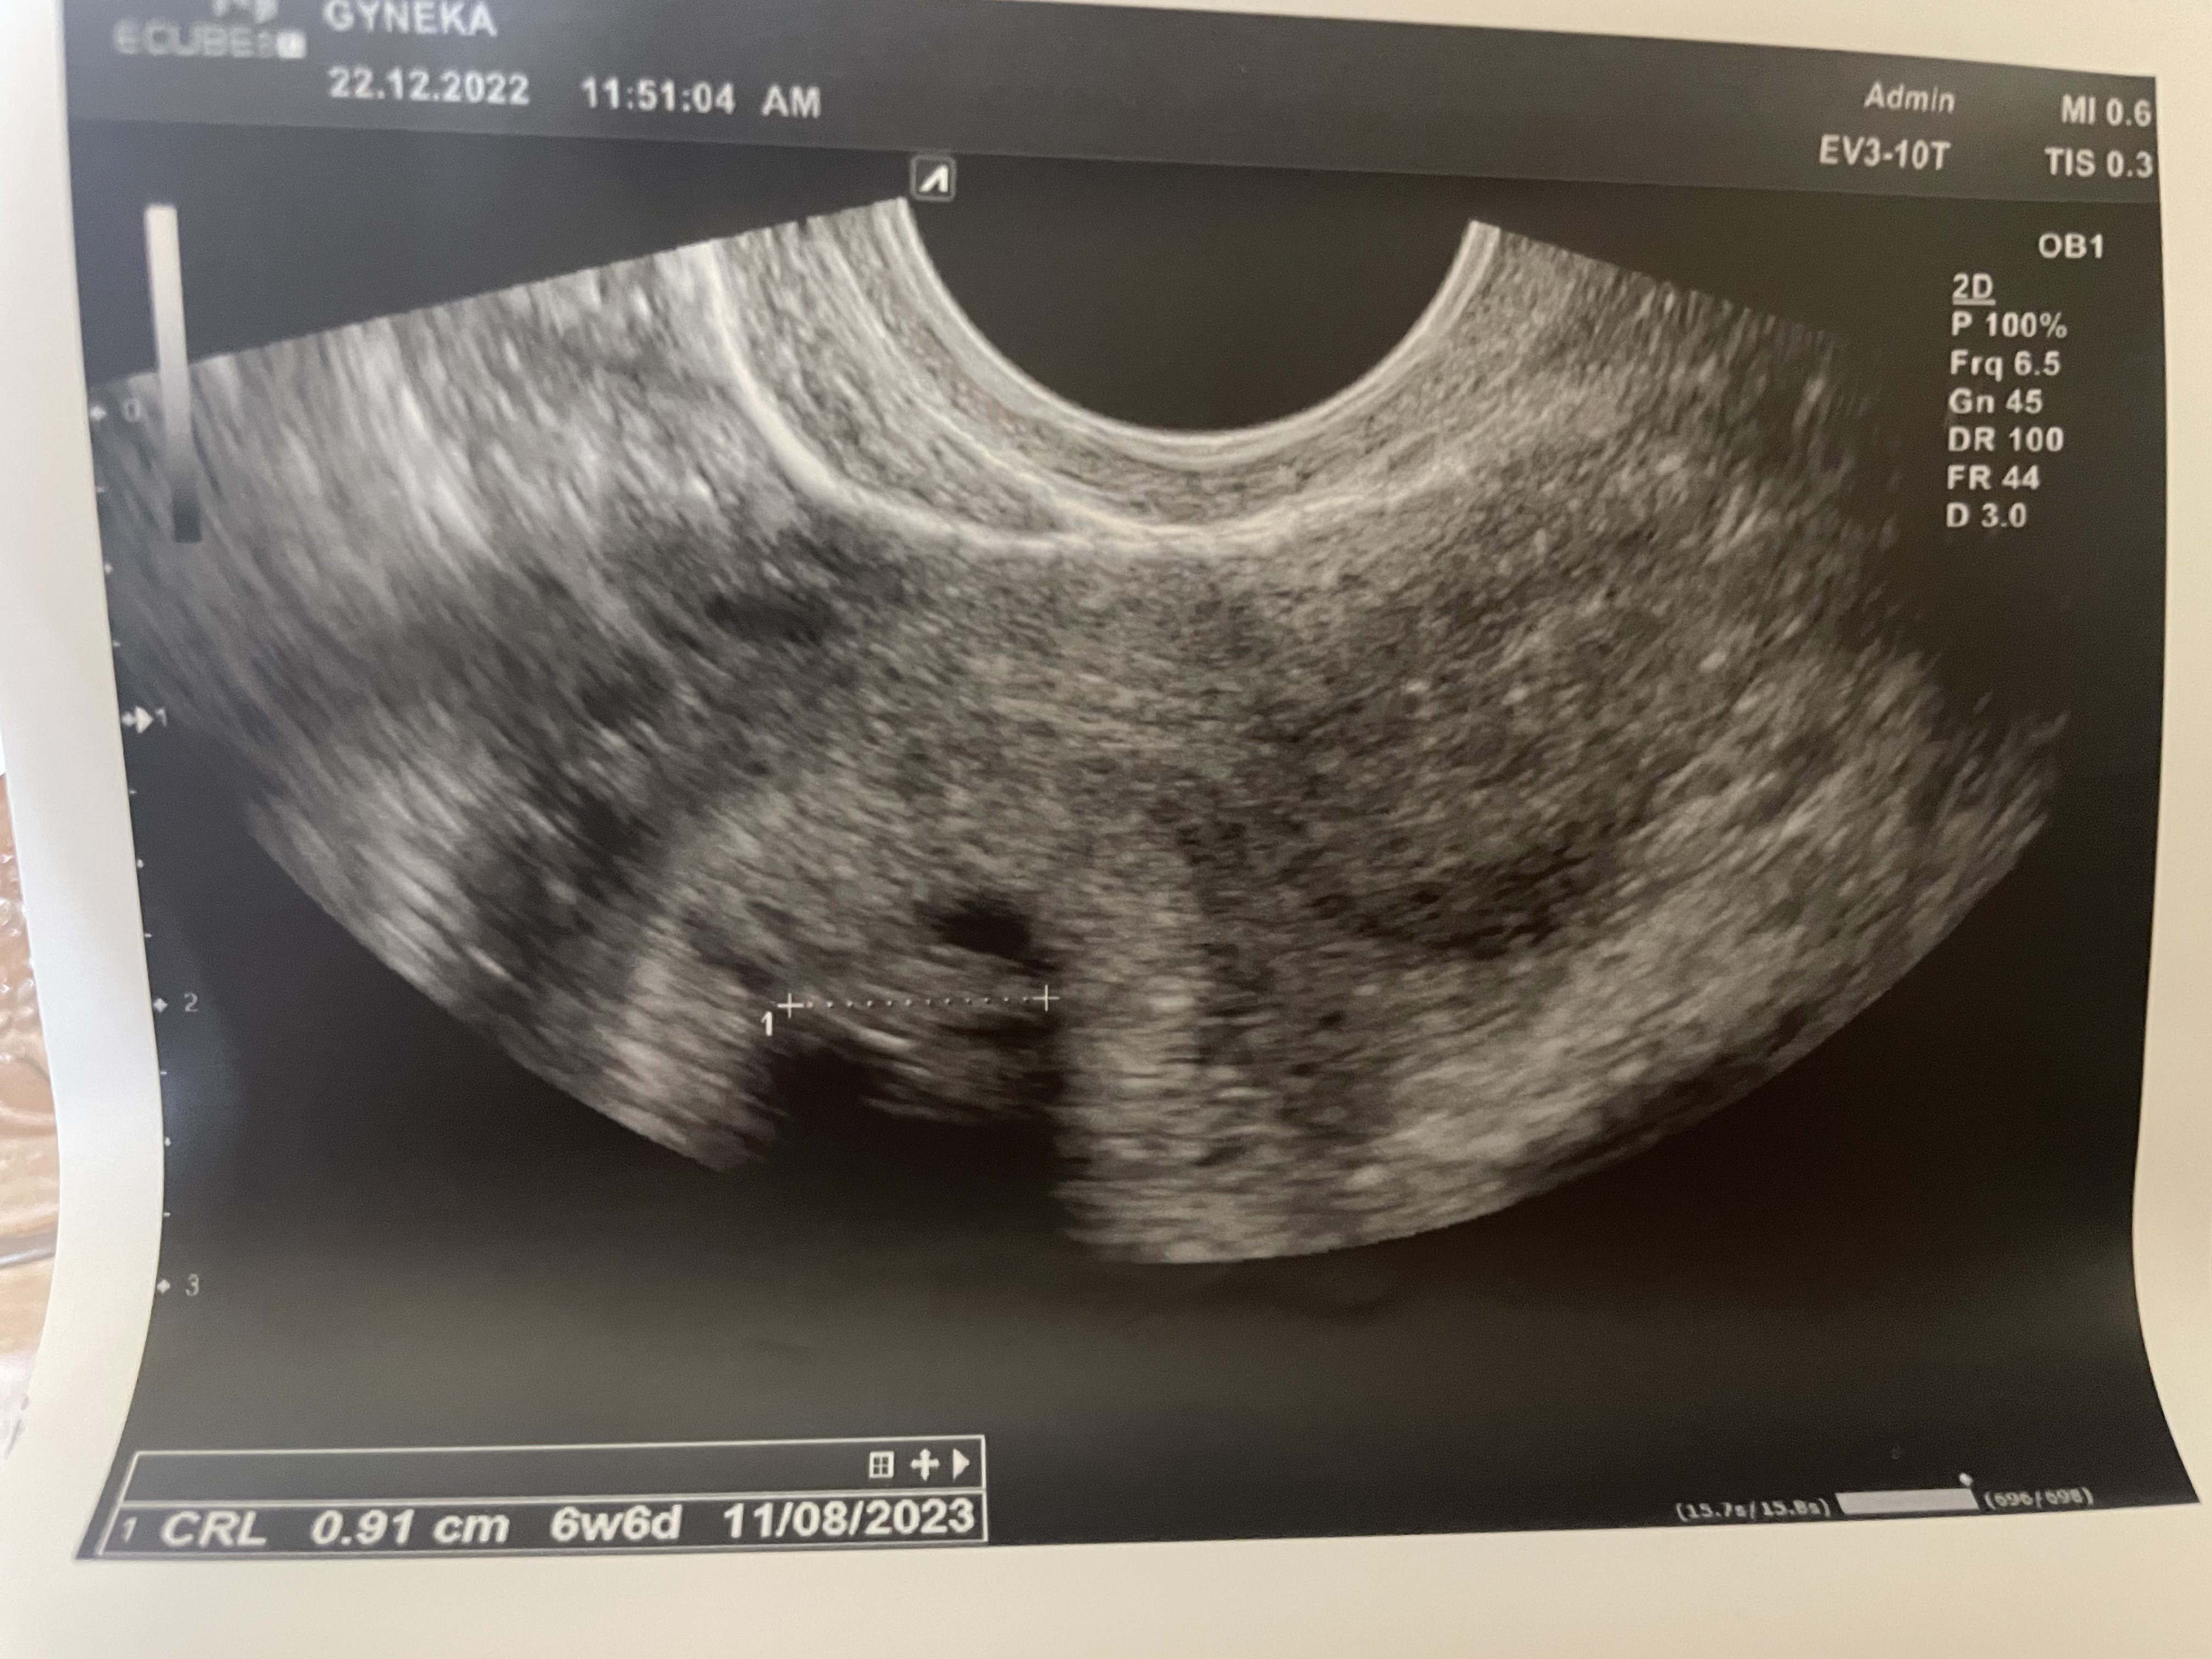

Sporo nas dzisiaj z wizytami. Tak się składa, że ja już po 😊. Dobrze sobie wyliczyłam, że dzisiaj 6+6, usg to potwierdziło . Termin na 11.08.23 ale karty ciąży jeszcze nie ma, jestem zapisana za 2 tygodnie jak zrobię wyniki 🥰 trzymam kciuki za resztę wizyt 🥰

Załączniki

• F73D14B8-53E3-417E-94C6-A36FB6103583.jpeg

F73D14B8-53E3-417E-94C6-A36FB6103583.jpeg

2 MB · Wyświetleń: 90